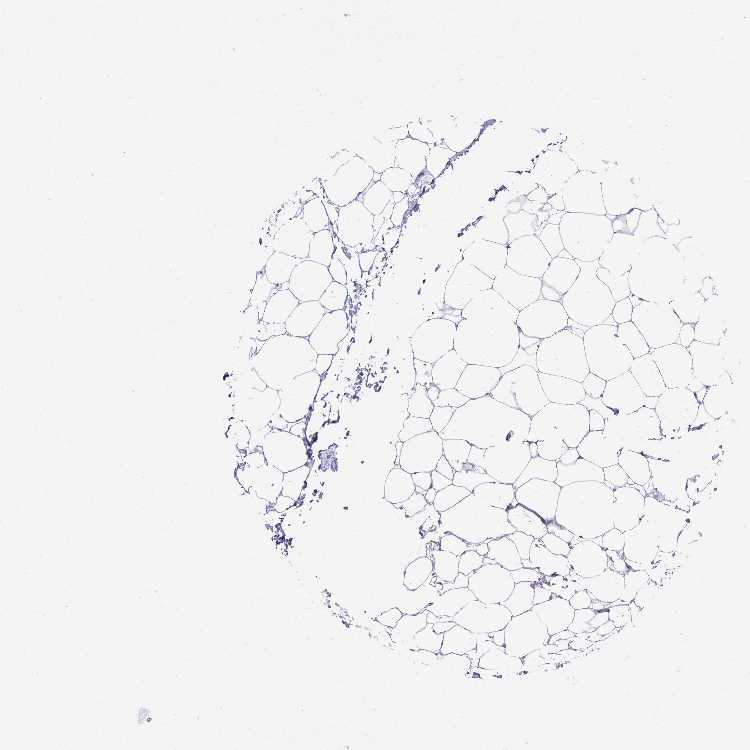

SOFT TISSUE 1 - Antibody stainingi

Antibody staining in the annotated cell types in the current human tissue is reported as not detected, low, medium, or high, based on conventional immunohistochemistry profiling in selected tissues. This score is based on the combination of the staining intensity and fraction of stained cells.

Each image is clickable and will lead to virtual microscopy that enables deeper exploration of all samples and also displays staining intensity scores, fraction scores and subcellular localization as well as patient and tissue information for each sample.

Antibody HPA062890

Chondrocytes Not detected

Fibroblasts Not detected

Peripheral nerve Not detected